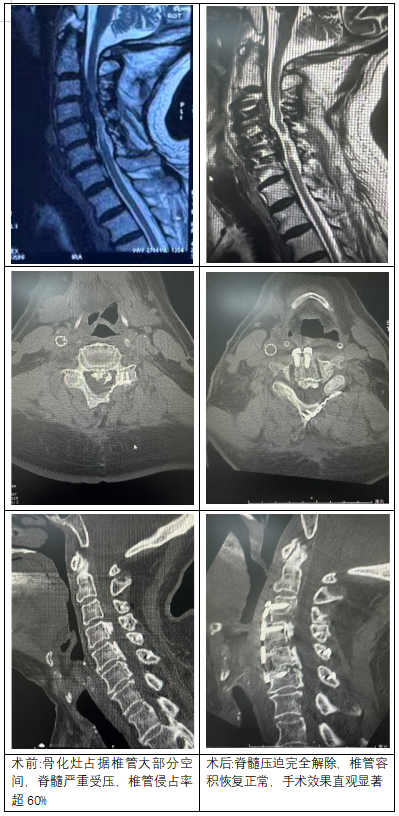

從術(shù)前術(shù)后影像對(duì)比可清晰看到,患者頸椎椎管狹窄部分被充分打開,脊髓壓迫完全解除,椎管容積恢復(fù)正常,手術(shù)效果直觀顯著。術(shù)后患者四肢麻木無力癥狀即刻緩解,次日便可在支具保護(hù)下下床活動(dòng),后續(xù)恢復(fù)狀況良好,生活質(zhì)量得到極大改善。